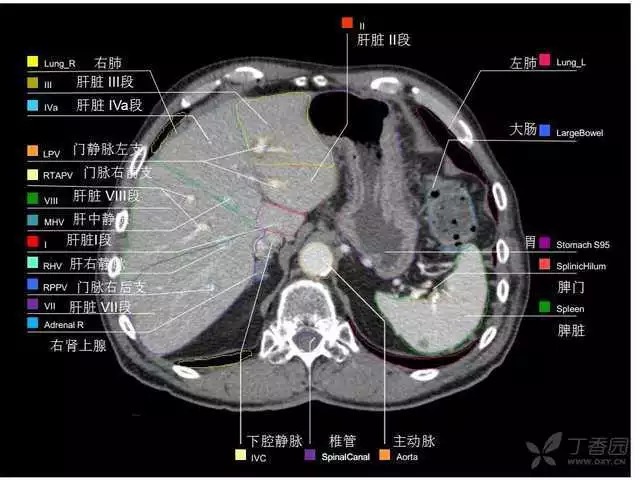

腹部肝脏高清CT断层的图谱

全腹部高清CT图谱,淋巴结彩色图谱,血管解剖图谱大汇总!

超声肝脏分叶及分段

肝脏分段和基本解剖学标志